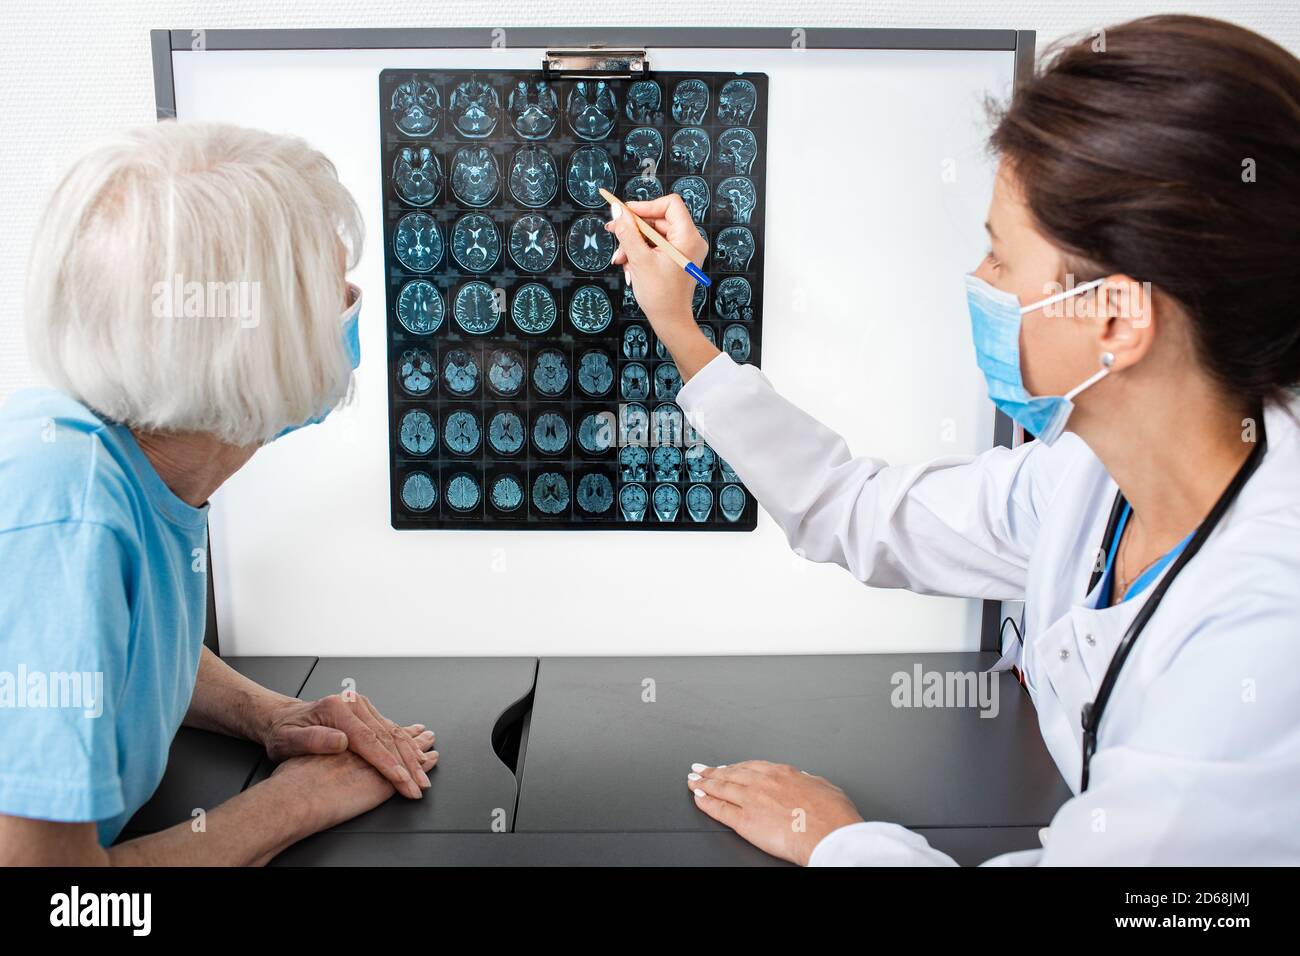

Elderly woman patient wearing a medical mask looks at the results of an MRI scan of her brain. Diagnosis of diseases and head injuries. DIAGNOSTICS OF Stock Photohttps://www.alamy.com/image-license-details/?v=1https://www.alamy.com/elderly-woman-patient-wearing-a-medical-mask-looks-at-the-results-of-an-mri-scan-of-her-brain-diagnosis-of-diseases-and-head-injuries-diagnostics-of-image382506334.html

Elderly woman patient wearing a medical mask looks at the results of an MRI scan of her brain. Diagnosis of diseases and head injuries. DIAGNOSTICS OF Stock Photohttps://www.alamy.com/image-license-details/?v=1https://www.alamy.com/elderly-woman-patient-wearing-a-medical-mask-looks-at-the-results-of-an-mri-scan-of-her-brain-diagnosis-of-diseases-and-head-injuries-diagnostics-of-image382506334.htmlRF2D68JME–Elderly woman patient wearing a medical mask looks at the results of an MRI scan of her brain. Diagnosis of diseases and head injuries. DIAGNOSTICS OF

doctor explains to an elderly woman the results of an MRI scan of her brain. Diagnosis of diseases and head injuries Stock Photohttps://www.alamy.com/image-license-details/?v=1https://www.alamy.com/doctor-explains-to-an-elderly-woman-the-results-of-an-mri-scan-of-her-brain-diagnosis-of-diseases-and-head-injuries-image382506338.html

doctor explains to an elderly woman the results of an MRI scan of her brain. Diagnosis of diseases and head injuries Stock Photohttps://www.alamy.com/image-license-details/?v=1https://www.alamy.com/doctor-explains-to-an-elderly-woman-the-results-of-an-mri-scan-of-her-brain-diagnosis-of-diseases-and-head-injuries-image382506338.htmlRF2D68JMJ–doctor explains to an elderly woman the results of an MRI scan of her brain. Diagnosis of diseases and head injuries